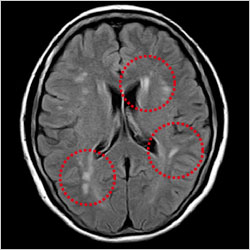

大脳白質病変

無症候性脳梗塞や大脳白質病変は、脳ドック受診者の約30%に発見されるといわれています。これらの高度なものは、高血圧、糖尿病、高脂血症などと同様に、脳卒中の危険因子です。また、くも膜下出血の原因の大部分は脳動脈瘤の破裂です。